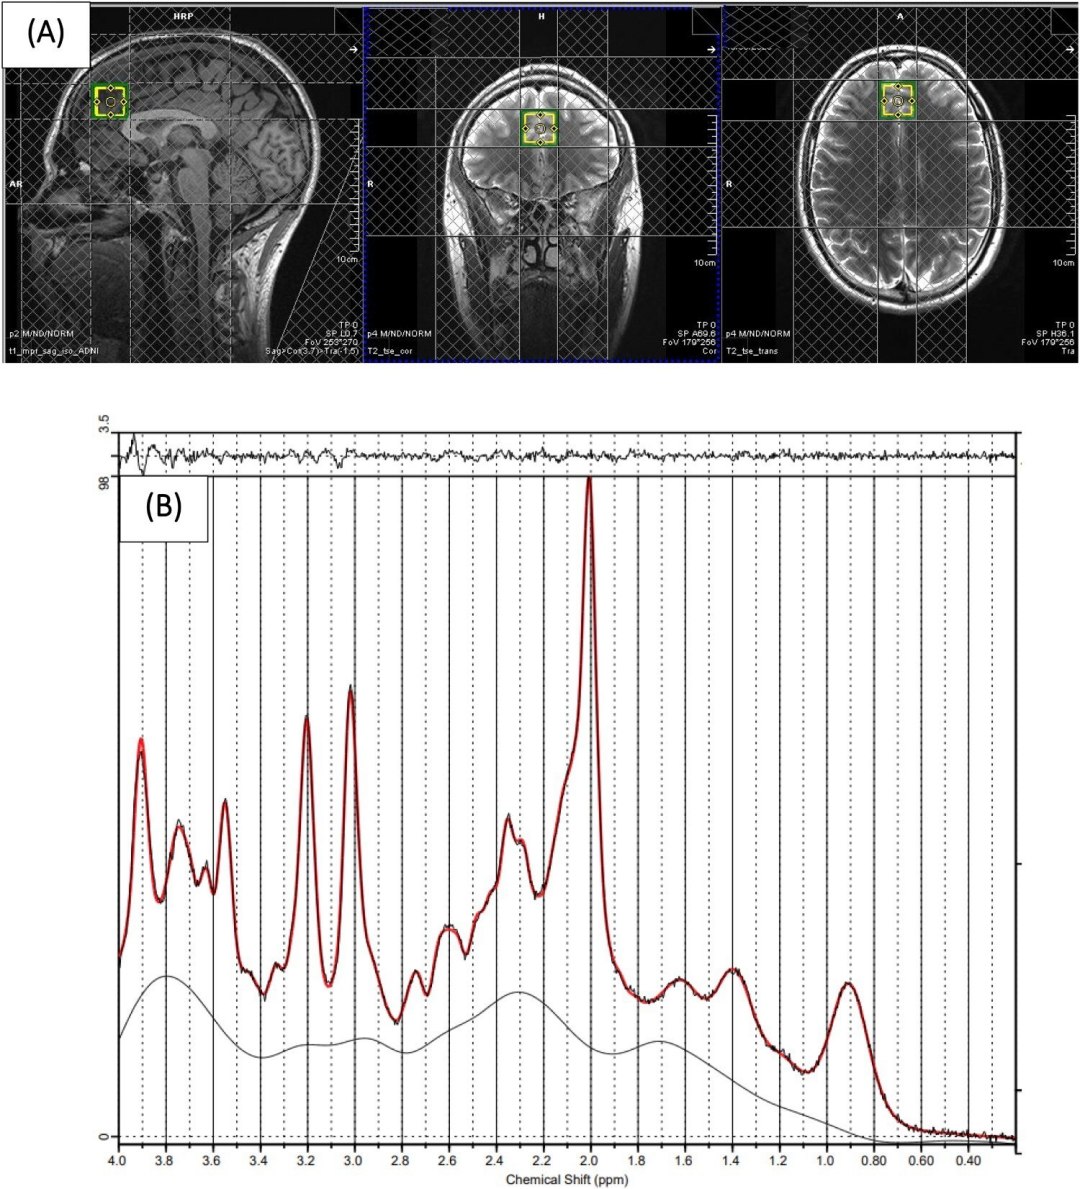

Exames cerebrais revelaram alterações nos neurotransmissores e no volume de substância cinzenta em pessoas que adotaram uma dieta pobre, em comparação com aquelas que seguiram uma alimentação de estilo mediterrâneo, que é considerada muito saudável.

O estudo revelou que, quando alguém tem uma dieta de baixa qualidade, há uma redução do ácido gama-aminobutírico (GABA) e aumento do glutamato - ambos neurotransmissores -, juntamente com redução do volume de substância cinzenta na área frontal do cérebro. Isso poderia explicar a associação entre o que comemos e como nos sentimos.